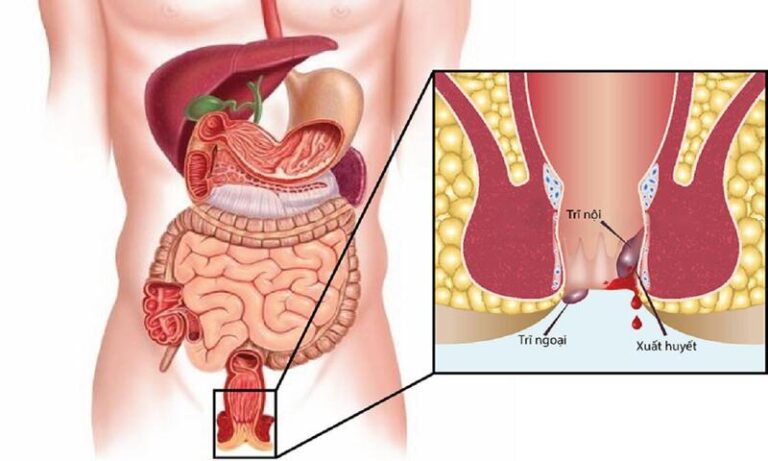

Trĩ Gây Thiếu Máu: Dấu Hiệu, Chi Phí & Phương Pháp Điều Trị Tại Tuyên Quang

Trĩ Gây Thiếu Máu: Nguyên Nhân, Dấu Hiệu Và Giải Pháp Điều Trị Trĩ gây thiếu máu là tình trạng nghiêm trọng xảy ra khi bệnh nhân bị…